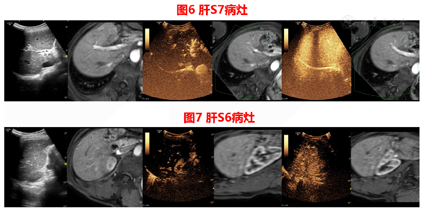

胆囊切除术前CT检查发现肝内病灶,胆囊切除术中病理结果证实S4段病灶为神经内分泌瘤,胆囊切除术后MRI确定剩余病灶,US-MRI容积导航影像融合联合超声造影进行病灶定位、引导、术后评估。

患者在2020年9月3日送手术室在复合麻醉下行US-MRI容积导航影像融合引导下经皮肝肿瘤微波消融治疗,见图8,图9。

US-CT/MRI影像融合容积导航技术结合了超声和CT/MRI的优点,同时避免了它们的缺点,这是一种可以在同一设置上同时显示超声和CT/MRI图像的技术。通常通过使用磁导航系统来实现,该系统允许协调两种不同的成像模式并允许它们在同一屏幕上显示。在位置感测单元的帮助下,CT/MRI图像随超声图像移动。在两个图像匹配良好之后,可以根据CT/MRI图像定位超声图像上的目标病变。将CT及MRI良好的空间分辨力与超声可实时动态显像的优点相结合,能够实现对病灶的精准定位,特别对常规超声显示困难的病灶,US-CT/MRI影像融合磁导航技术显示出良好优越性[6,7]。

本例患者在常规超声未发现异常病灶,于是在融合成像辅助定位下,对磁共振对应区域进行超声造影,确定了病灶位置,进行消融及术后即时评估。术后患者规律复查,消融效果良好,病灶未见活性。